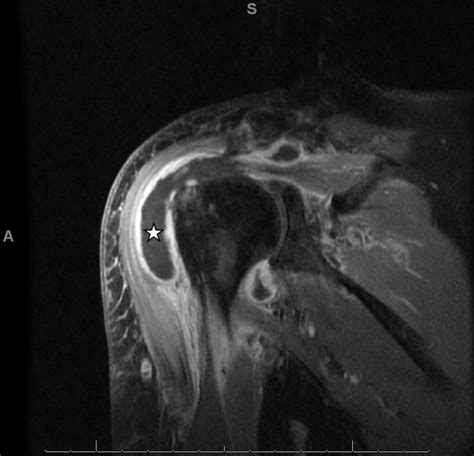

• Imaging Tests: X-rays, MRI, or ultrasound to visualize the joint and detect any abnormalities.

• glenohumeral joint effusion mri